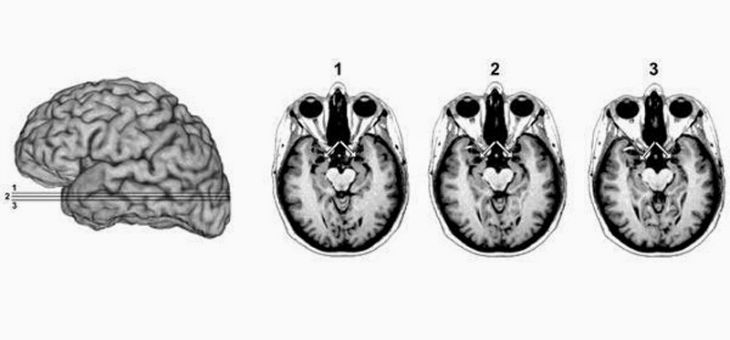

According To Science, You Will Be Fearless If You Remove This Part Of Your Brain

Researchers in the 1930’s conducted a research on animals and discovered that when they removed a certain part of a monkey’s brain, the animals turned fearless: they could approach snakes and bat them around with sticks without fear. They even played with the hissing tongues of the snakes. The experiment has been repeated numerous times in animals and the scientists have reached a consensus: when the amygdala is removed, animals lose any sense of fear.

The same experiment was conducted on humans and the results were similar, according to a study in the journal, Current Biology.

Justin Feinstein, lead author of the study and clinical neuropsychologist at the University of Iowa says that, “There’s not very many humans with this sort of brain damage, luckily for us, we had access to a patient, SM, and we studied her different fear behaviors and we read her personal diaries.”

Patient SM has holes where her amygdala should be due to lipoid proteinosis, a rare condition. According to the researchers, she reacted the same way the monkeys did; she has no fear of creatures like spiders and snakes that alarm most people ordinarily. She also tends to put her life at risk. On one occasion, she was attacked by a man with a knife while walking alone through a park, “the following day, she again walked through the same park,” Mr. Feinstein said.

He and his colleagues are trying to coach the patient into being more careful. They believe that if they understand how SM’s mind works, they may be able to develop therapies for people with excessive amounts of fear, for example war veterans. “We may be able to dampen the effects of the amygdala. We can do that through psychotherapy and possibly through medication.” he said.